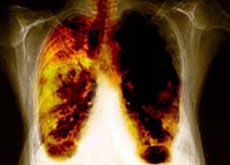

Entro il 2015, l'OMS vuole raddoppiare il numero di test - 700'000 nel 2006 - per la tubercolosi Keystone

Esperti svizzeri hanno lanciato un appello affinché il personale sanitario sia meglio protetto contro la tubercolosi. Una misura indispensabile nel quadro del programma di lotta globale contro la malattia.

La tubercolosi è principalmente una malattia del sistema respiratorio che si trasmette per le vie aeree (tosse e starnuti).

I sintomi sono tosse, spesso accompagnata da sangue, perdita di peso, dolore toracico, febbre e sudorazione notturna.